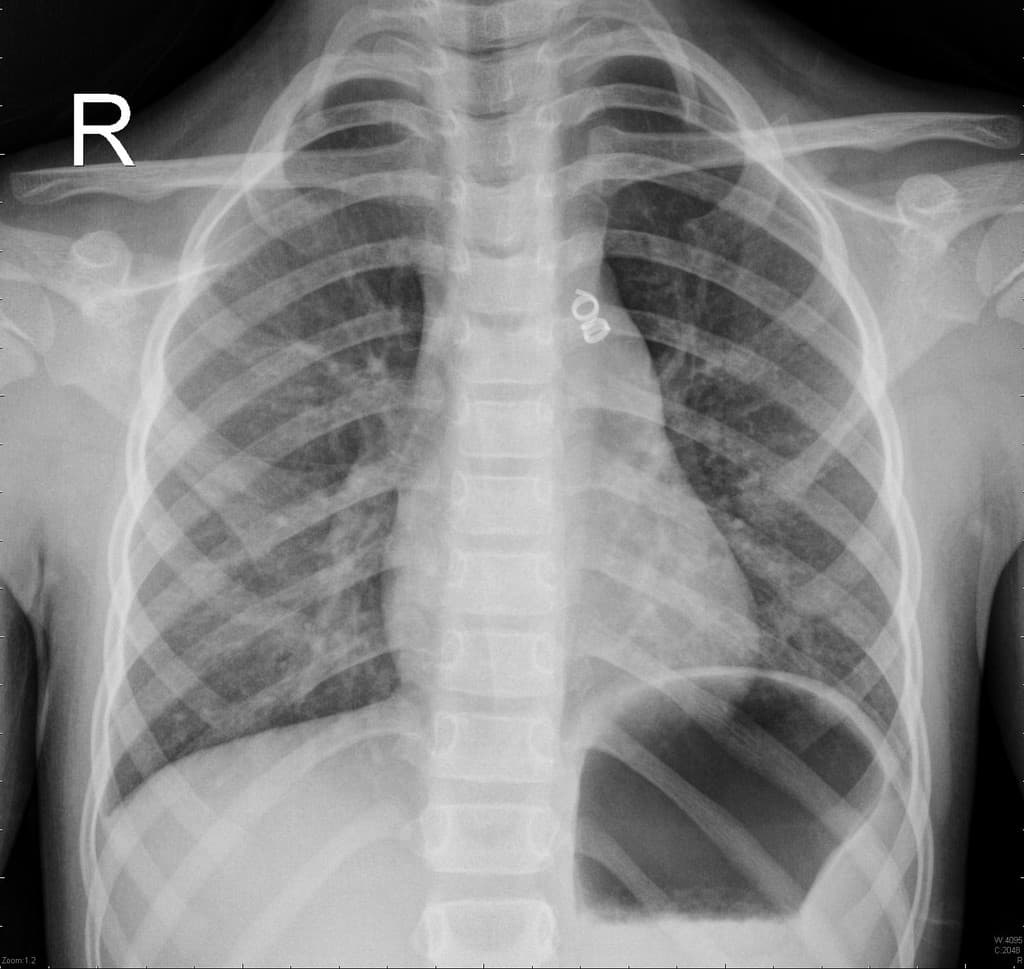

Khó thở.

- Thông liên nhĩ lỗ thứ phát (secundum atrial septal defect).

- Hẹp van động mạch phổi, đã thực hiện nong van động mạch phổi bằng bóng (s/p balloon pulmonary valvuloplasty).

- Động mạch phổi chính (main pulmonary artery) giãn.

- Hẹp đoạn gần động mạch phổi trái (proximal left pulmonary artery).

- Thất phải (right ventricle) giãn.